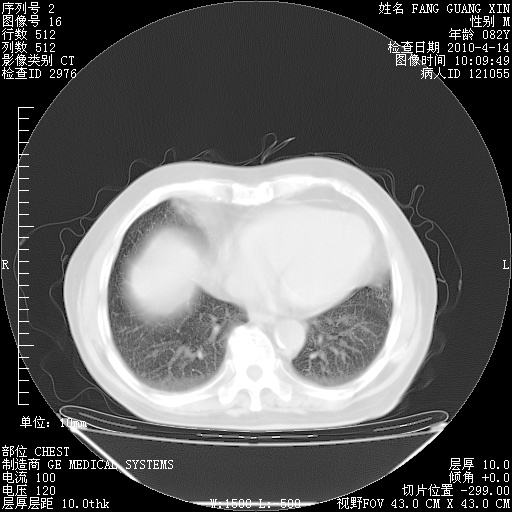

4月14日肺部CT

23.JPG

24.JPG

25.JPG

26.JPG